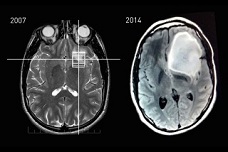

MRI data showing Mr Keating’s astrocytoma tumor before and after surgical removal (Image courtesy of Steven Keating)

IN 2007, out of sheer curiosity, Steven Keating had an MRI scan that revealed only a slight abnormality near his brain’s smell center, which he was advised to have re-evaluated in a few years. A second scan, in 2010, showed no change, suggesting that the abnormality was most likely benign. Mr Keating, currently a graduate student in the Department of Mechanical Engineering and based at the MIT Media Lab, had joined a research study that included an MRI scan, and he asked that the scan’s raw data be returned to him.

Now Mr Keating says that his curiosity saved his life — and that his experience with cancer has fueled a strong interest in advocating for open health data. While the second scan provided reassurance, his knowledge of the abnormality ultimately led to the detection of a baseball-sized tumor that was removed this past August.

He requested and obtained the video of his 10-hour surgery. A tissue biopsy confirmed that his tumor was an IDH1-mutant malignant astrocytoma, a type of brain cancer in which the mutated IDH enzyme leads to the production of 2HG, a novel, oncogenic metabolite.

Spectroscopy screening of Mr. Keating’s brain before and after his surgery showed the reduction of 2HG. These scans were also shared with Mr. Keating, at his request.